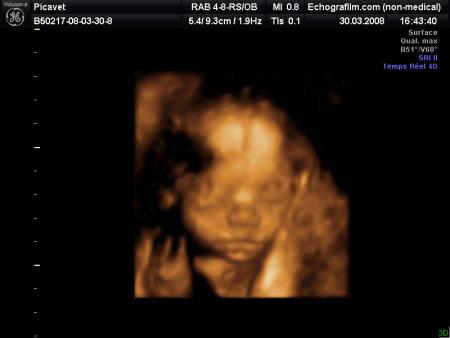

voila ma petite soeur elle va s appelle lorena elle et belle